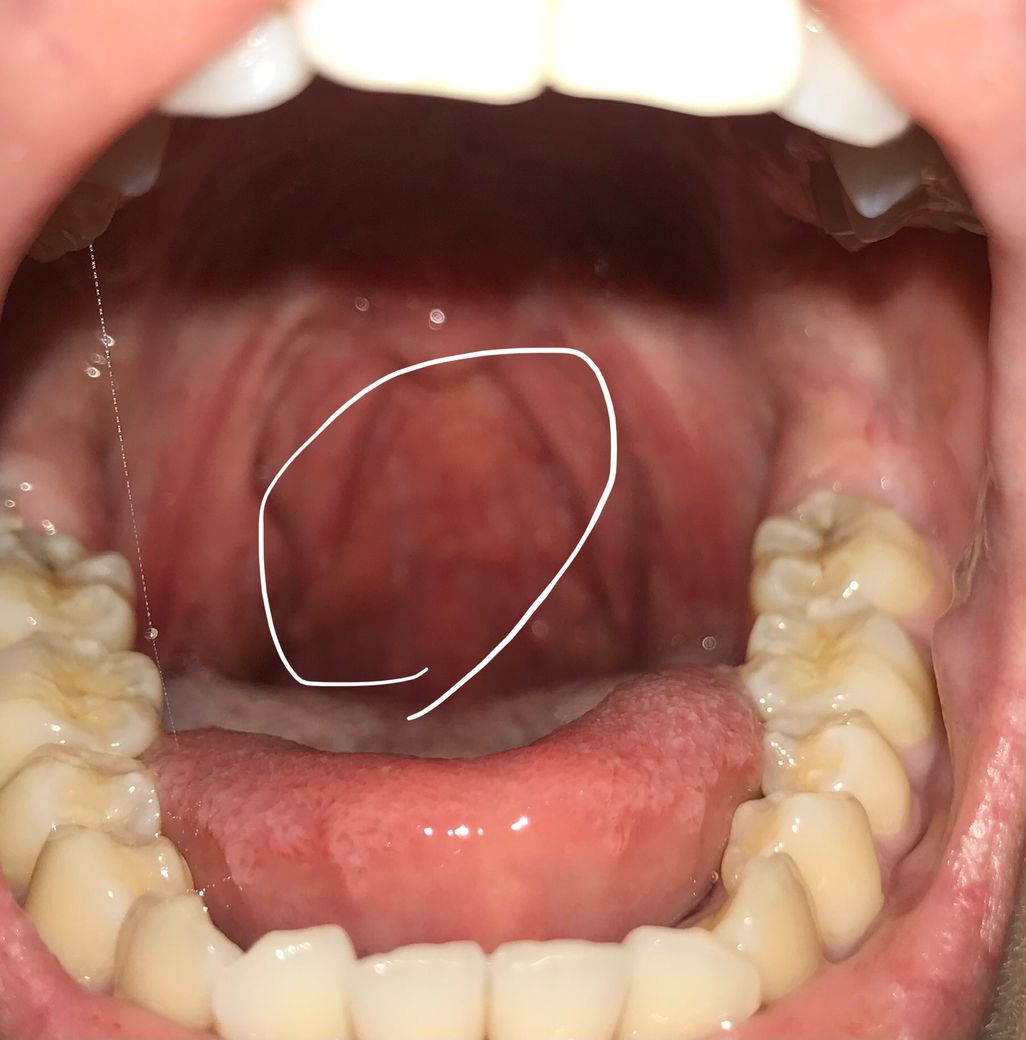

목 안에 뭐가 부은 것 처럼 있는데 한번 봐주세요 ㅠㅠ

저렇게 오돌토돌 나있는건 정상인거 아는데 그런 오돌토돌 느낌 보다는 좀 더 크게 부은 느낌으로 나 있어요 ㅠㅠ 목이 부은건가요???!

사진상으로 보면 크게 문제가 잇는것처럼 보이진 않습니다. 만약 목이 부엇다면 편도쪽이 부은거일수도 있습니다.

목안에 편도가 부어서 나타나는 증상일 가능성이 있기에 이비인후과에 방문하여 진료를 받아 보길권합니다.